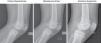

These methods include those used by Caton–Deschamps, Blackburne–Peel and Koshino–Sugimoto17–22 (Fig. 1).

Data were recorded in an Excel 2013 (Microsoft office®) spreadsheet. The variables used included age, side, sex and degree of knee flexion. The following scales were also measured for each knee: Caton–Deschamps (normal values from 0.6 to 1.3), Blackburne–Peel (normal values from 0.8 to 1.0) and Koshino–Sugimoto (normal values from 0.99 to 1.2 for knees with a flexion of from 30° to 90°) (Fig. 2). 3 measurements were taken independently by each observer to calculate each one of the 3 scales in the X-ray images, without knowledge of either patient data or the measurements of the other observers. The observers were an orthopaedic surgeon trained in knee surgery and 2 orthopaedic surgeons trained in paediatric orthopaedia. One of the 2 latter surgeons repeated the measurements 24 weeks after the first measurement without knowledge of patient data or the results of the previous measurements. Agreement was then evaluated using the intraclass correlation coefficient. The measurements of each observer for each scale were compared to determine interobserver variability for each scale, while the coefficient between 2 measurements by the same observer at 2 different times was calculated for intraobserver variability. The coefficients were interpreted according to Table 1. Taking into account possible changes in the variability of coefficients with ossification at different ages, they were divided according to age group. The unit of analysis was each knee. The median and interquartile ranges are presented to describe the scales because they did not have a normal distribution. The range between percentiles 5 and 95 is also shown (P5–P95), as a proposal of normal values for the population according to age group.